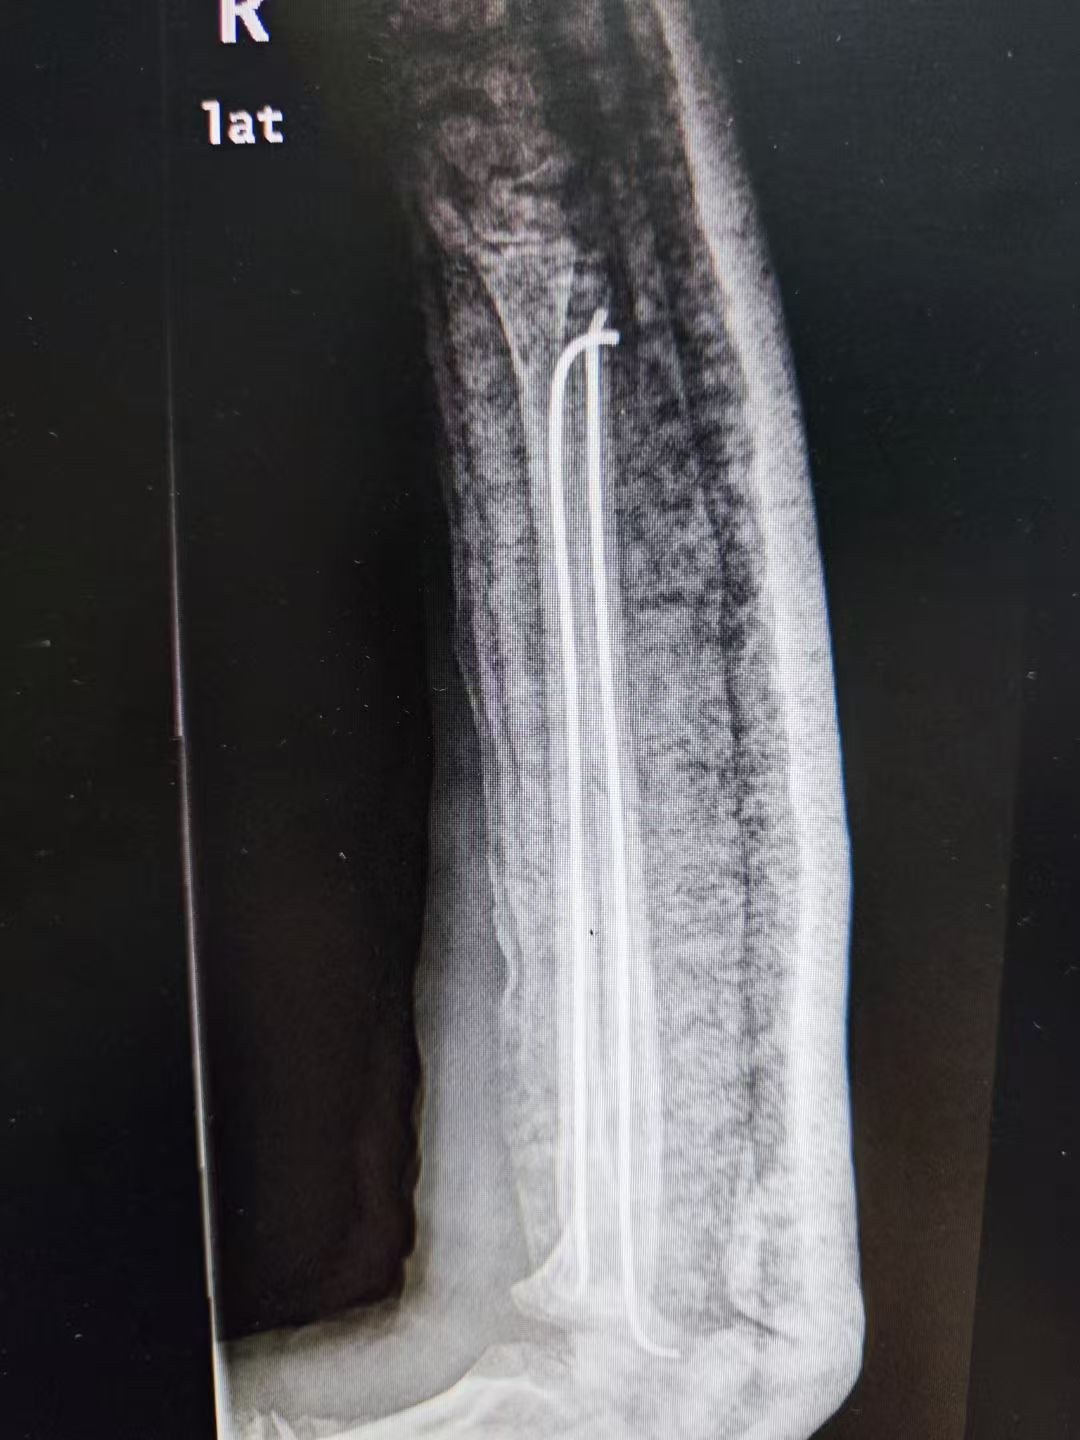

儿童尺桡骨双骨折闭合复位微创弹性髓内针内固定

儿童股骨干骨折闭合复位微创弹性髓内针内固定